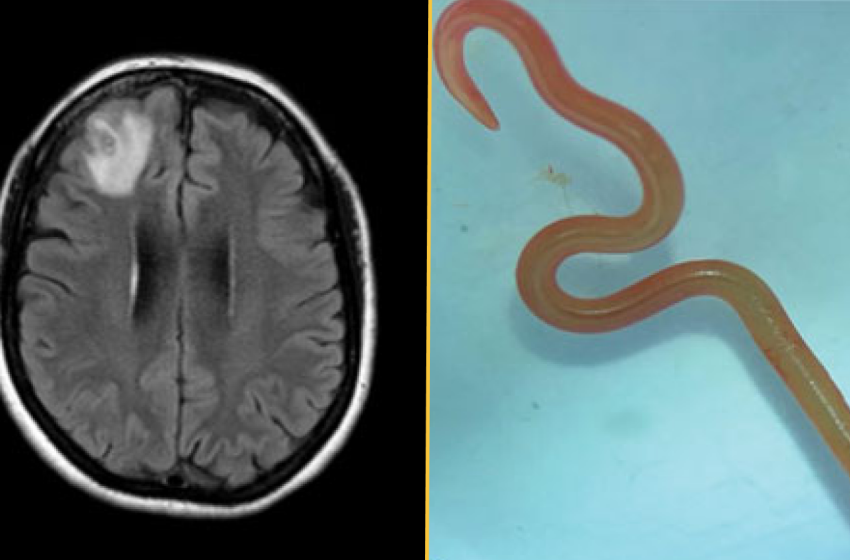

The diagnosis: About a year after her initial hospital visit, the woman began to develop signs of depression and had episodes of forgetfulness. Physicians ordered an MRI of her brain and detected a lesion on the right frontal lobe. They then performed an open biopsy to expose and examine the damaged area. That’s when they discovered “a stringlike structure” inside the lesion, which they identified as a living parasitic worm called a helminth, according to a report of her case.

The worm was bright red and measured about 3 inches (80 millimeters) long and 0.04 inches (1 millimeter) thick.

What makes the case unique: The doctors identified the helminth as a third-stage larva of Ophidascaris robertsi, a type of parasitic nematode native to Australia. The adult worms reproduce inside carpet pythons (Morelia spilota), but the nematode can infect other animals during the larval stages of its life cycle.